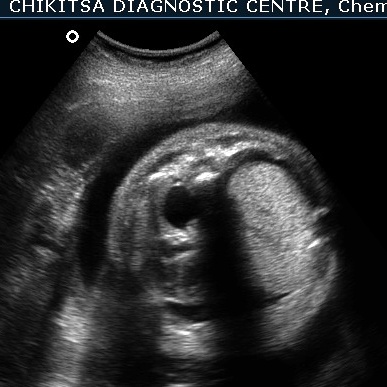

There is hydrops due to cardiac failure : bilateral pleural effusion, a small amount of ascites and generalised edema in the sub-cutaneous tissue.

Since the heart and the great veins draining into the right heart (SVC and IVC) are compressed, the heart remains small in size. This reduces the venous return to the right atrium, and also the stroke volume of the heart. This is manifest as cardiac failure and consequent hydrops.